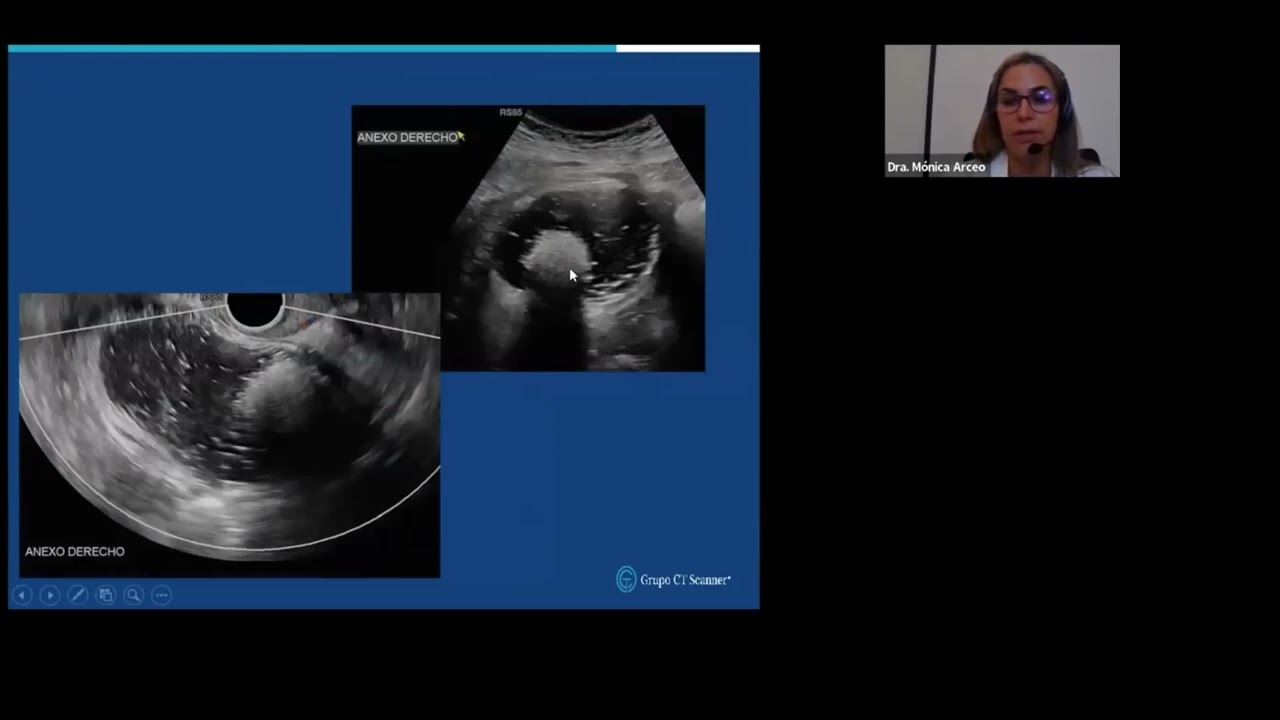

❞𝗖𝗹𝗮𝘀𝗶𝗳𝗶𝗰𝗮𝗰𝗶𝗼́𝗻 𝗢-𝗥𝗔𝗗𝗦 𝗲𝗻 𝗽𝗮𝘁𝗼𝗹𝗼𝗴𝗶́𝗮 𝗼𝘃𝗮́𝗿𝗶𝗰𝗮❞ 𝗨𝗹𝘁𝗿𝗮𝘀𝗼𝗻𝗶𝗱𝗼 𝘆 𝗿𝗲𝘀𝗼𝗻𝗮𝗻𝗰𝗶𝗮 𝗺𝗮𝗴𝗻𝗲́𝘁𝗶𝗰𝗮